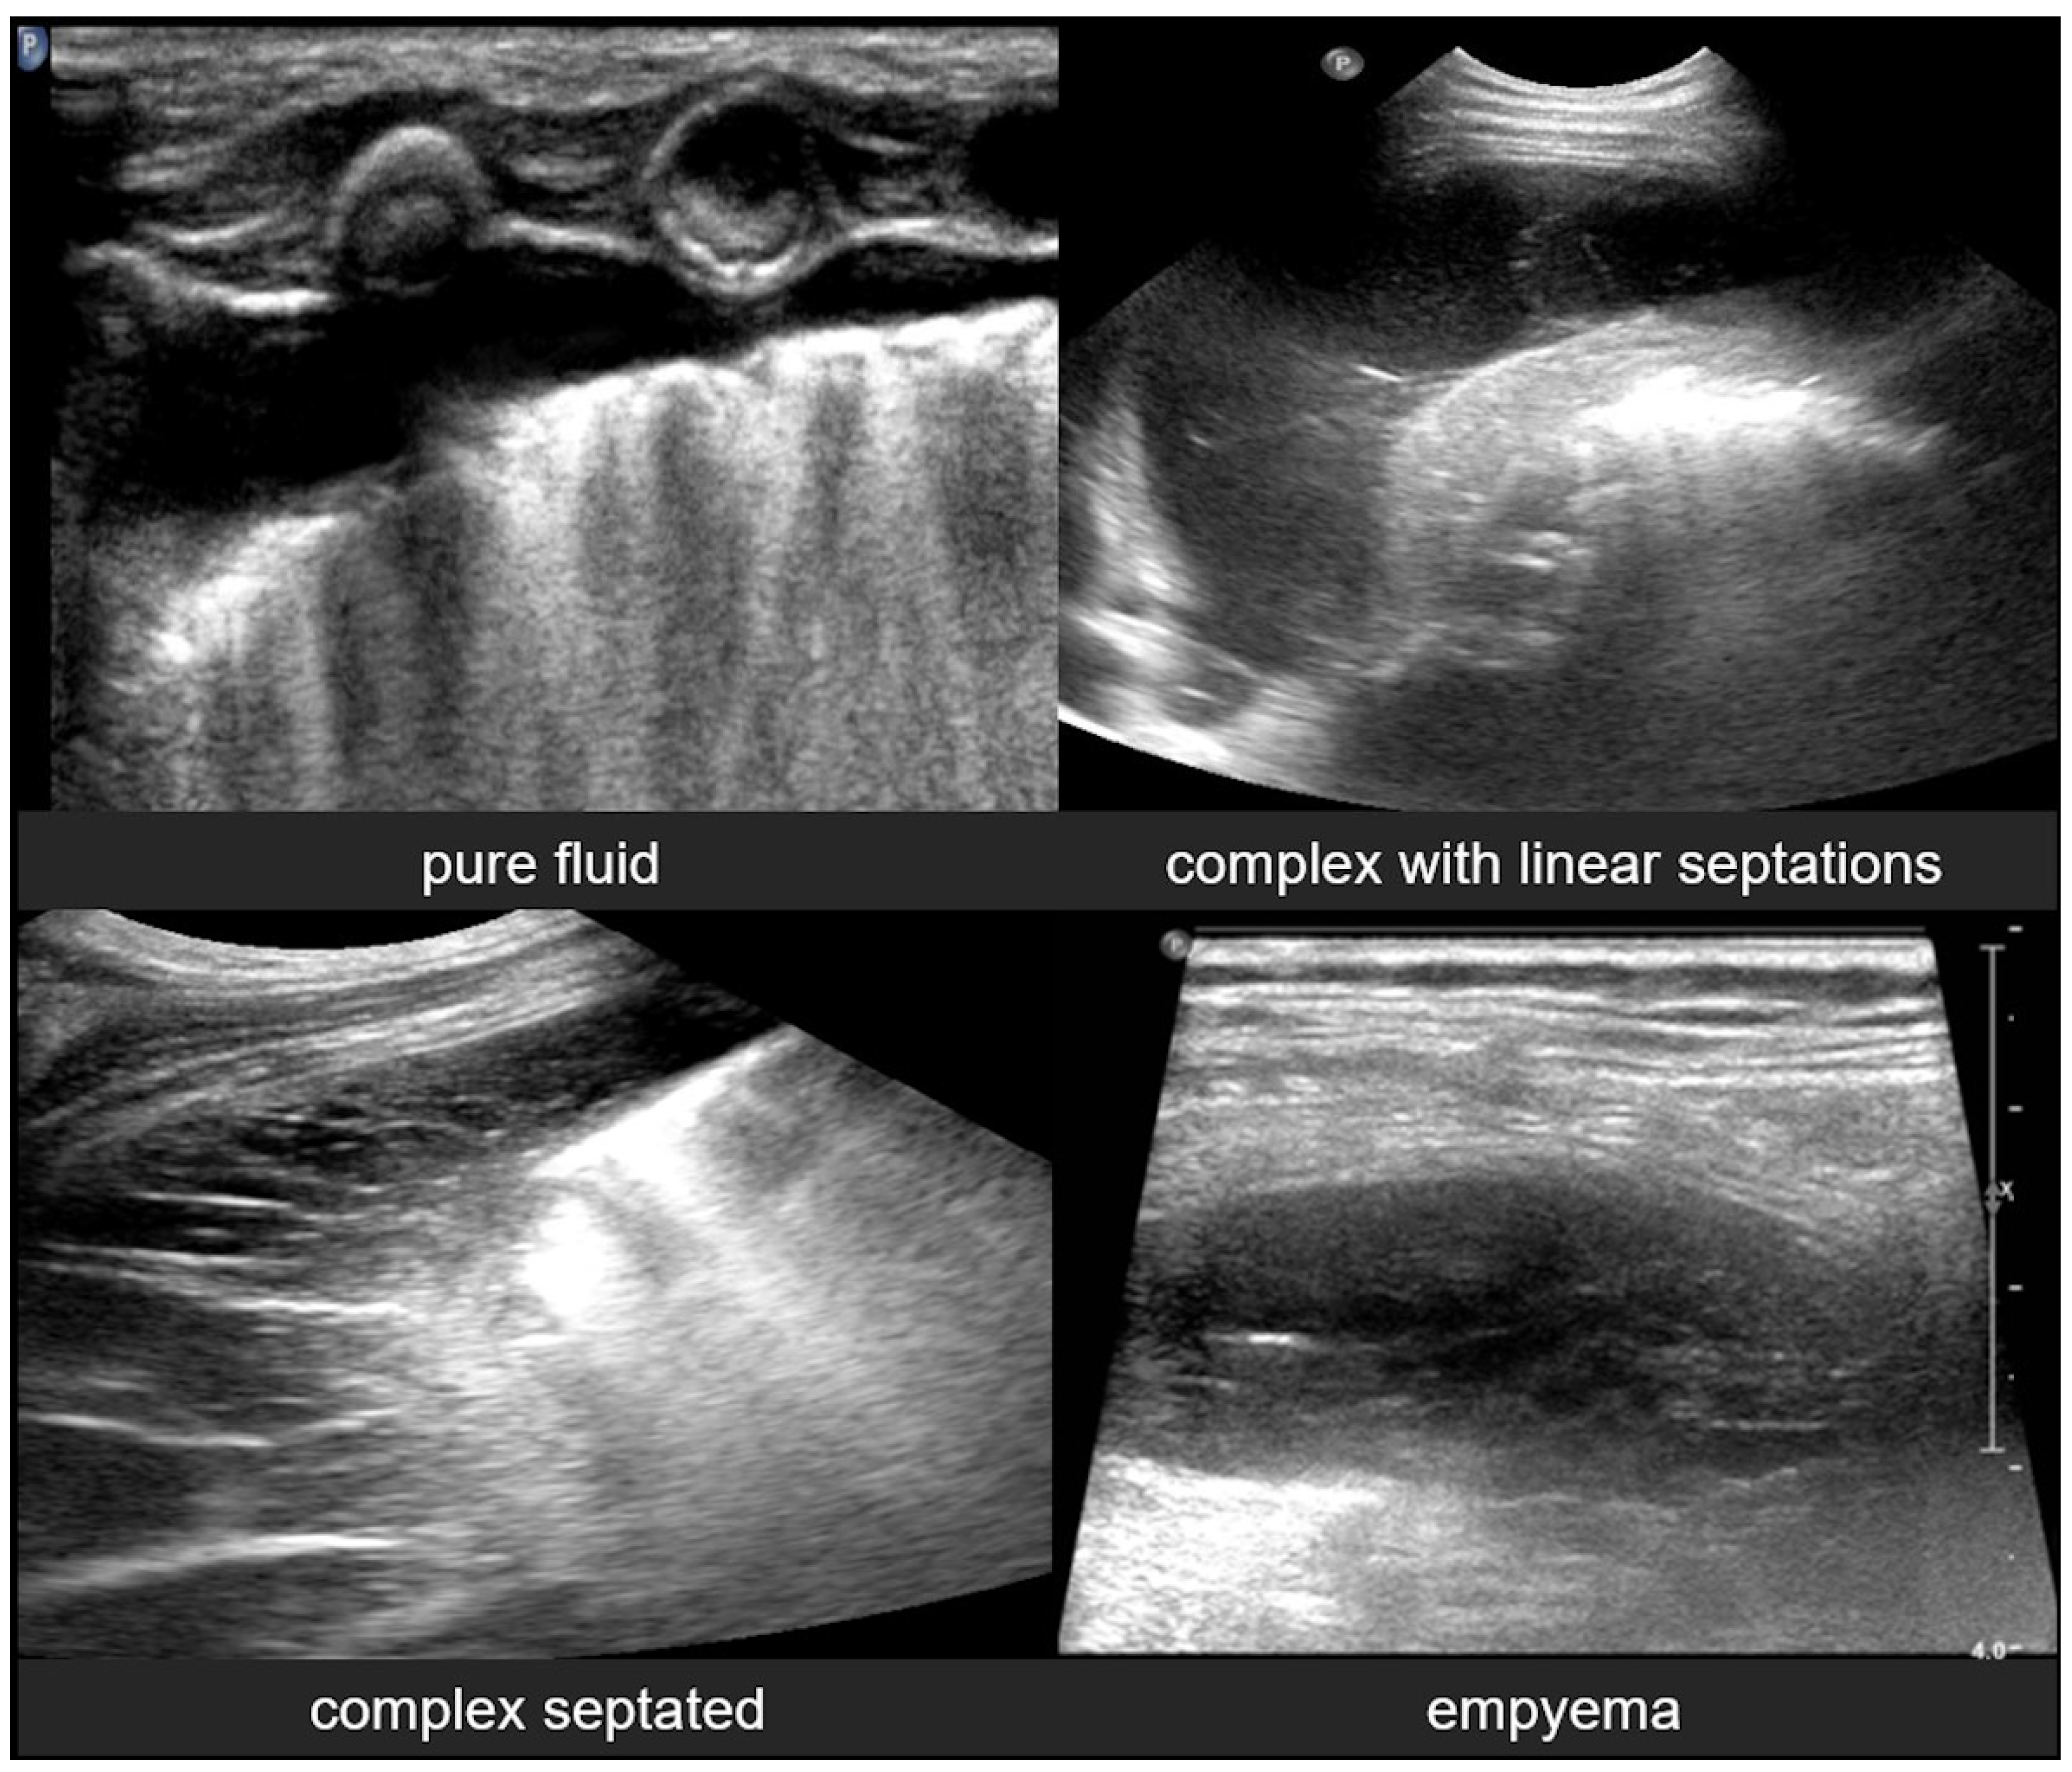

3.2.10. Pleural Effusion

Pleural effusion, defined as the accumulation of fluid in the pleural space, can be easily detected by LUS, which is highly sensitive and able to identify even small volumes of fluid (as little as 5–20 mL). In contrast, effusions greater than 175–250 mL must typically be present for the detection of pleural effusion by conventional chest X-rays, although lateral decubitus views may detect effusions of approximately 50 mL. A pure pleural effusion typically appears as an anechoic collection located between the parietal and visceral pleura, often seen as a clear, dark space (fluid) that allows for the visualization of underlying lung structures and diaphragm movement [13,20,35,54].

In contrast, complicated effusions may exhibit internal echogenicity due to the presence of fibrin, debris, or infection. Identifying the nature of the effusion, in other words whether it is simple effusion or complicated, is critical for clinical decision-making, and may help indicate the need for drainage, antibiotic therapy, or surgical intervention. Thus, LUS can be considered to play a pivotal role in both the diagnosis and management of pleural effusions, particularly in neonates and critically ill patients [10,23].

3.2.11. Empyema

Empyema refers to the accumulation of purulent material within the pleural space, typically as a complication of pneumonia or other infectious processes involving the lungs. In neonates and pediatric patients, empyema is a significant cause of morbidity and often presents with respiratory distress, fever, and signs of pleural effusion. LUS is a valuable tool for the evaluation of empyema, because it often offers greater sensitivity than chest X-rays and can be used to effectively guide both diagnosis and management [6,12,54].

LUS findings in empyema typically reveal a complex pleural effusion rather than a simple anechoic collection. The effusion often contains internal echogenic debris, fibrinous strands, and multiple septations that create a multiloculated appearance. These features help differentiate empyema from uncomplicated effusions. In some cases, the adjacent lung may appear consolidated, and pleural thickening is commonly observed. The consolidated lung adjacent to the empyema may show reduced or absent air bronchograms, reflecting impaired ventilation due to compression or infection.

Timely recognition of pleural empyema is critical, because it requires aggressive intervention, including antibiotics and often image-guided or surgical drainage. Thus, lung ultrasound not only facilitates early detection of pleural empyema, but also plays a crucial role in procedural planning, monitoring therapeutic response, and reducing reliance on ionizing radiation in vulnerable pediatric populations (Figure 23) [6,12].

Figure 23.

Pleural effusions.